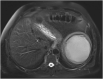

Isolated splenic cystic echinococcosis is a rare condition. In Greece the number of cases has declined substantially in the last 20 years. The spleen is the second most common extrahepatic site of cystic echinococcosis. Albendazole is safe, but mebendazole can be used as a substitute, in case of adverse reaction. Our patient was diagnosed with isolated splenic echinococcal cyst, during the investigation for newly diagnosed type 2 diabetes mellitus. We opted for elective splenectomy, based on a risk assessment due to the patient's working conditions, and treatment with albendazole represented a safety measure until surgery was possible. The patient developed acute hepatocellular injury to albendazole after eight weeks of treatment. This was confirmed through rechallenge with albendazole after discontinuation of the drug. Postsplenectomy the treatment with mebendazole proved to be safe with no adverse reactions. Even though, albendazole is known to be safe, monitoring of hepatic enzymes and full blood count should be offered. In case of toxicities, mebendazole with or without praziquantel can be used. Toxicity to mebendazole can be similar to albendazole but a trial is worthwhile. In our patient, treatment with mebendazole was uneventful.